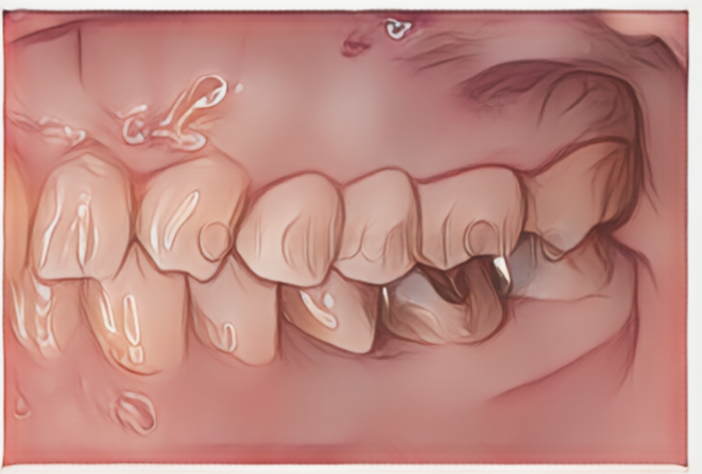

前歯に関しては、より高い審美性を求められることが多いので、次の症例のように透明感の高いジルコニアセラミックによるブリッジ修復を行うことが多いです。

患者様は60代女性。前歯がかぶせ物の中で割れてしまっており、抜歯後にジルコニアセラミックを用いたブリッジを行うこととなりました。

ジルコニアセラミッククラウン 14.3〜16.5万円/本(税込)

治療後のリスクとしては、強い衝撃で欠けたり割れたりする可能性があります。必ずしもご希望通りの見た目にならない事があります。また、根の問題が生じた場合、根管治療の必要性が生じる可能性があります。

こちらはブリッジの土台となる歯は神経のない歯となりますが、このタイミングでインプラントを用いてしまうと、将来隣の神経のない歯が割れてしまった時に次の一手が非常に難しいものとなります。ご相談の上で、ブリッジによる治療を選択することになりました。